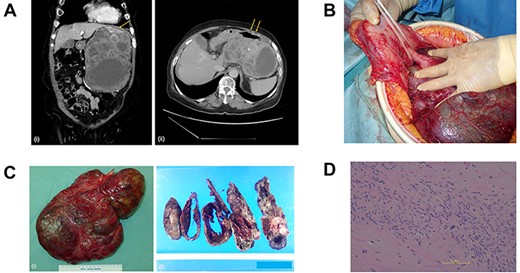

A woman in her seventies was referred to our surgical unit, presenting with a history of pulsation on her abdomen and a left abdominal mass that she noticed one month earlier. She had no history of abdominal disorders or surgery. Computed tomography showed a huge mass (16 × 10 × 20 cm) arising extraluminally from the stomach (Fig. 1a).

(A) Computed tomography scan of the abdomen before the primary surgery (i, coronal view; ii, axial view). The large pleomorphic mass measures 16×10×20 cm and is adjacent to the stomach (arrow). (B) Intraoperative inspection shows a large tumor pedunculated from the dorsal wall of the upper body of the stomach. (C) Postoperative specimen (i) of the gastric pedunculated GIST. The tumor shows (ii) pleomorphism of solid and cystic areas, calcification, hemorrhage, and necrosis. (D) The tumor consists mostly of spindle cells arranged in interlacing bundles and partially of epithelioid cells with severe atypia compared to usual GISTs.

The tumor was diagnosed as GIST by an immunohistochemical examination of the specimen from endoscopic ultrasound fine-needle aspiration. We started neoadjuvant chemotherapy using imatinib but discontinued it two months later due to febrile neutropenia. The patient underwent surgery, and intraoperative inspection showed a large tumor pedunculated from the dorsal wall of the upper body of the stomach (Fig. 1b). There was no visual evidence of metastasis or dissemination. The tumor was resected, including the pedicle and a small contiguous part of the stomach, without capsule rupture.

Grossly, the tumor (30 × 20 × 6 cm in size) proliferated from the gastric muscularis propria. The mass showed a mixture of solid and cystic areas, calcification, hemorrhage, and necrosis (Fig. 1c). Histologically the mitotic index was over 10 per 50 high-power fields (Fig. 1d). The final diagnosis was GIST, categorized as high risk of recurrence by all major prognostic criteria. The surgical margin was negative.